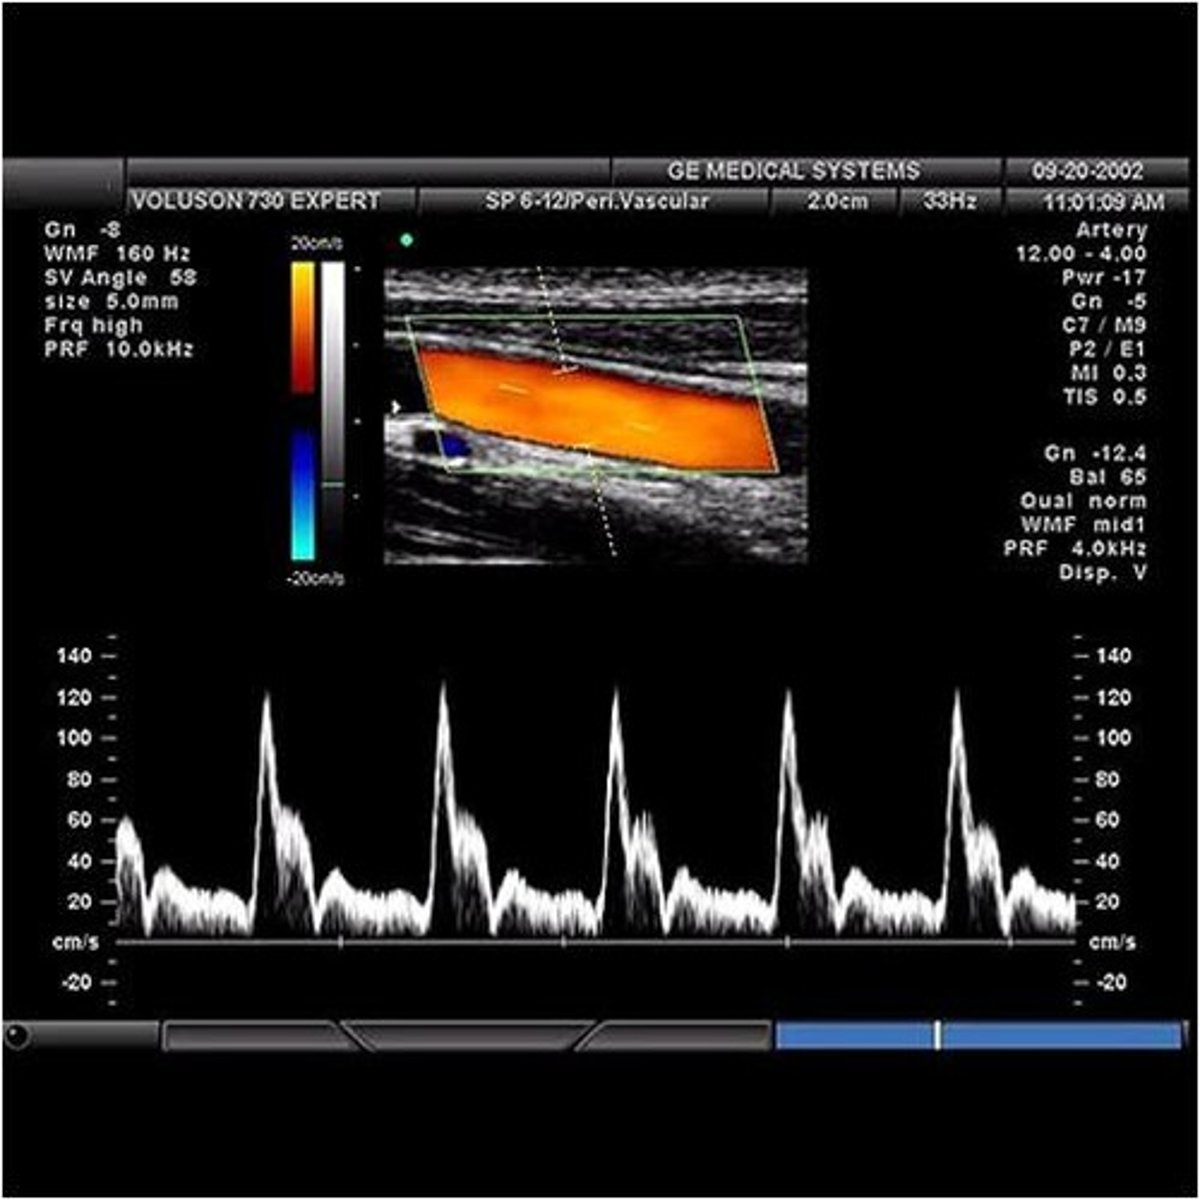

Unlike the cerebrovascular system that feeds the brain and requires continuous blood flow even during diastole when the heart is relaxing, the peripheral vascular system that feeds blood to the upper extremities (arms) and lower extremities (legs)has a very different waveform pattern. The term that best describes the normal waveform pattern associated with the peripheral arterial system of the legs is...

uniphasic

biphasic

triphasic

quadriphasic